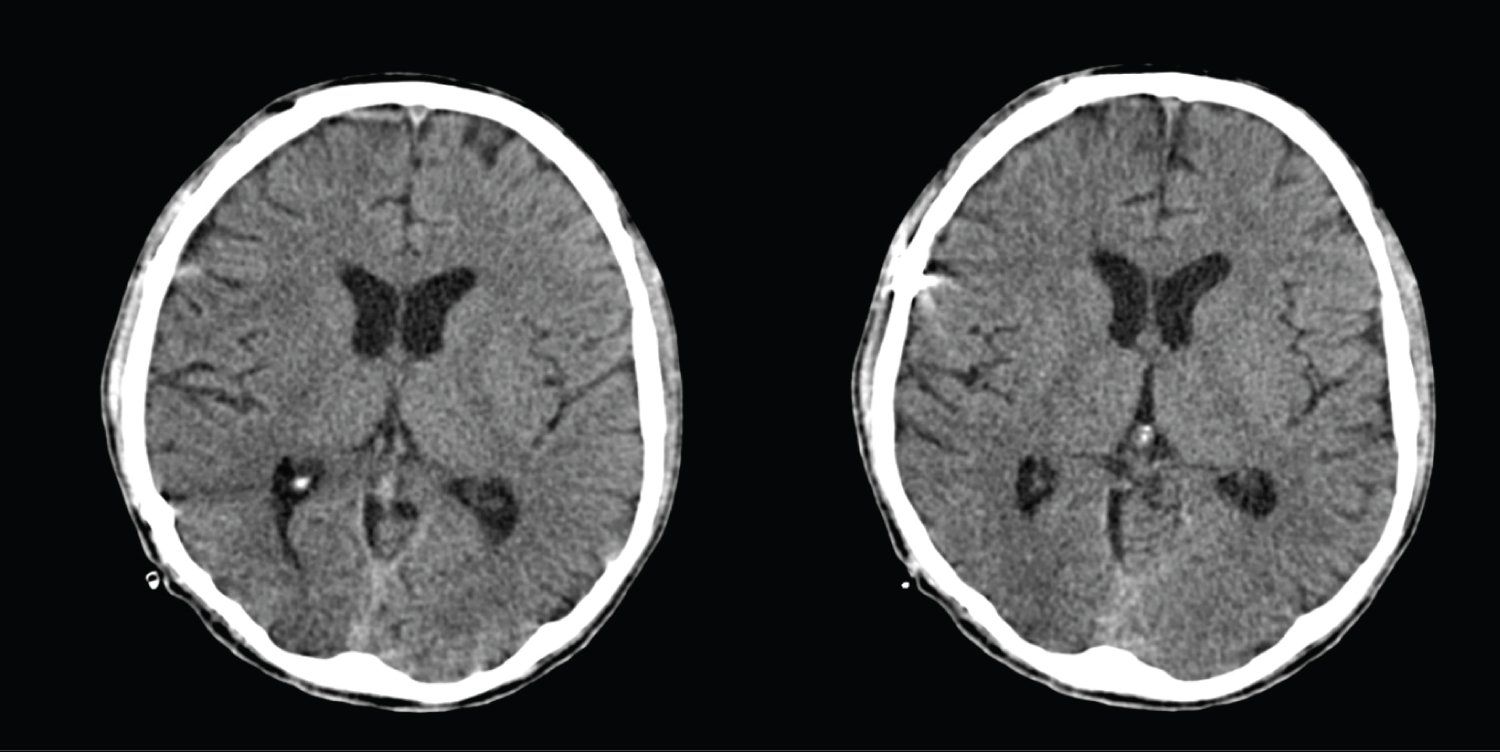

A 29-year-old male admitted due to severe head injury after a motor vehicular accident (MVA). On clinical assessment, the initial Glasgow Coma Scale (GCS) was 5/15 (E1V1M3). His blood pressure was140/94, pulse rate of 103/min, respiratory rate at 14/min. His pupils were unequal. His right pupil was 3 mm reactive to light and left pupil was 6 mm unreactive to light. There were multiple facial fractures involving left maxillary and left inferior orbital fractures. CT scan showed multiple intracranial haemorrhages with contusions and right sided subdural haematoma with interhemispheric and tentorial subdural haematoma (Figure 1). There were also a C6 left facet joint fracture extending into the left lamina with presence of retropulsed fracture segment in the spinal canal, and bilateral first rib fractures.

Figure 1: Punctate hyperdensity at both right and left frontal lobe in keeping with contusional bleeding. Extra-axial hyperdensity along the frontoparietal region in keeping with subdural bleed. It measures 0.35 cm in maximum thickness. Subdural bleed along the left tentorium cerebelli. No midline shift. View Figure 1